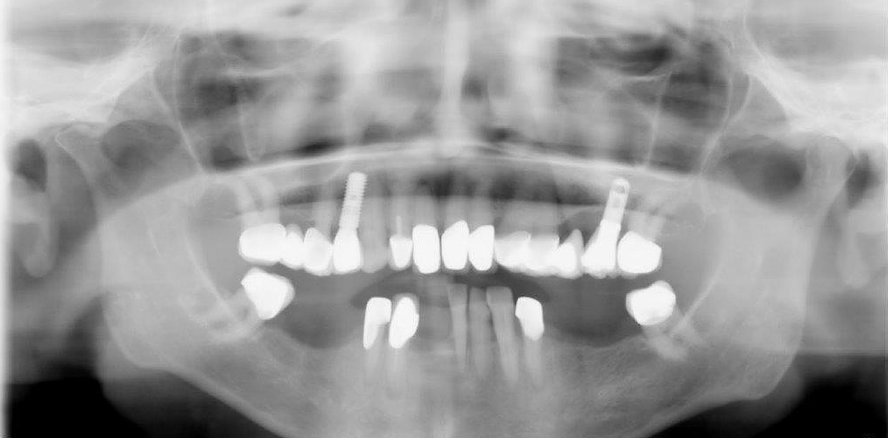

Exemplarisch werden Fälle zweier Patienten vorgestellt. Anhand der Bilddokumentation ergibt sich die Beschreibung der Implantationstechnik und des Verlaufes.

Fall 1: 28-jährige Patientin, ohne klinische oder lokale Befunde.

Fall 2: 72-jährige Patientin, ohne klinische und lokale Befunde.